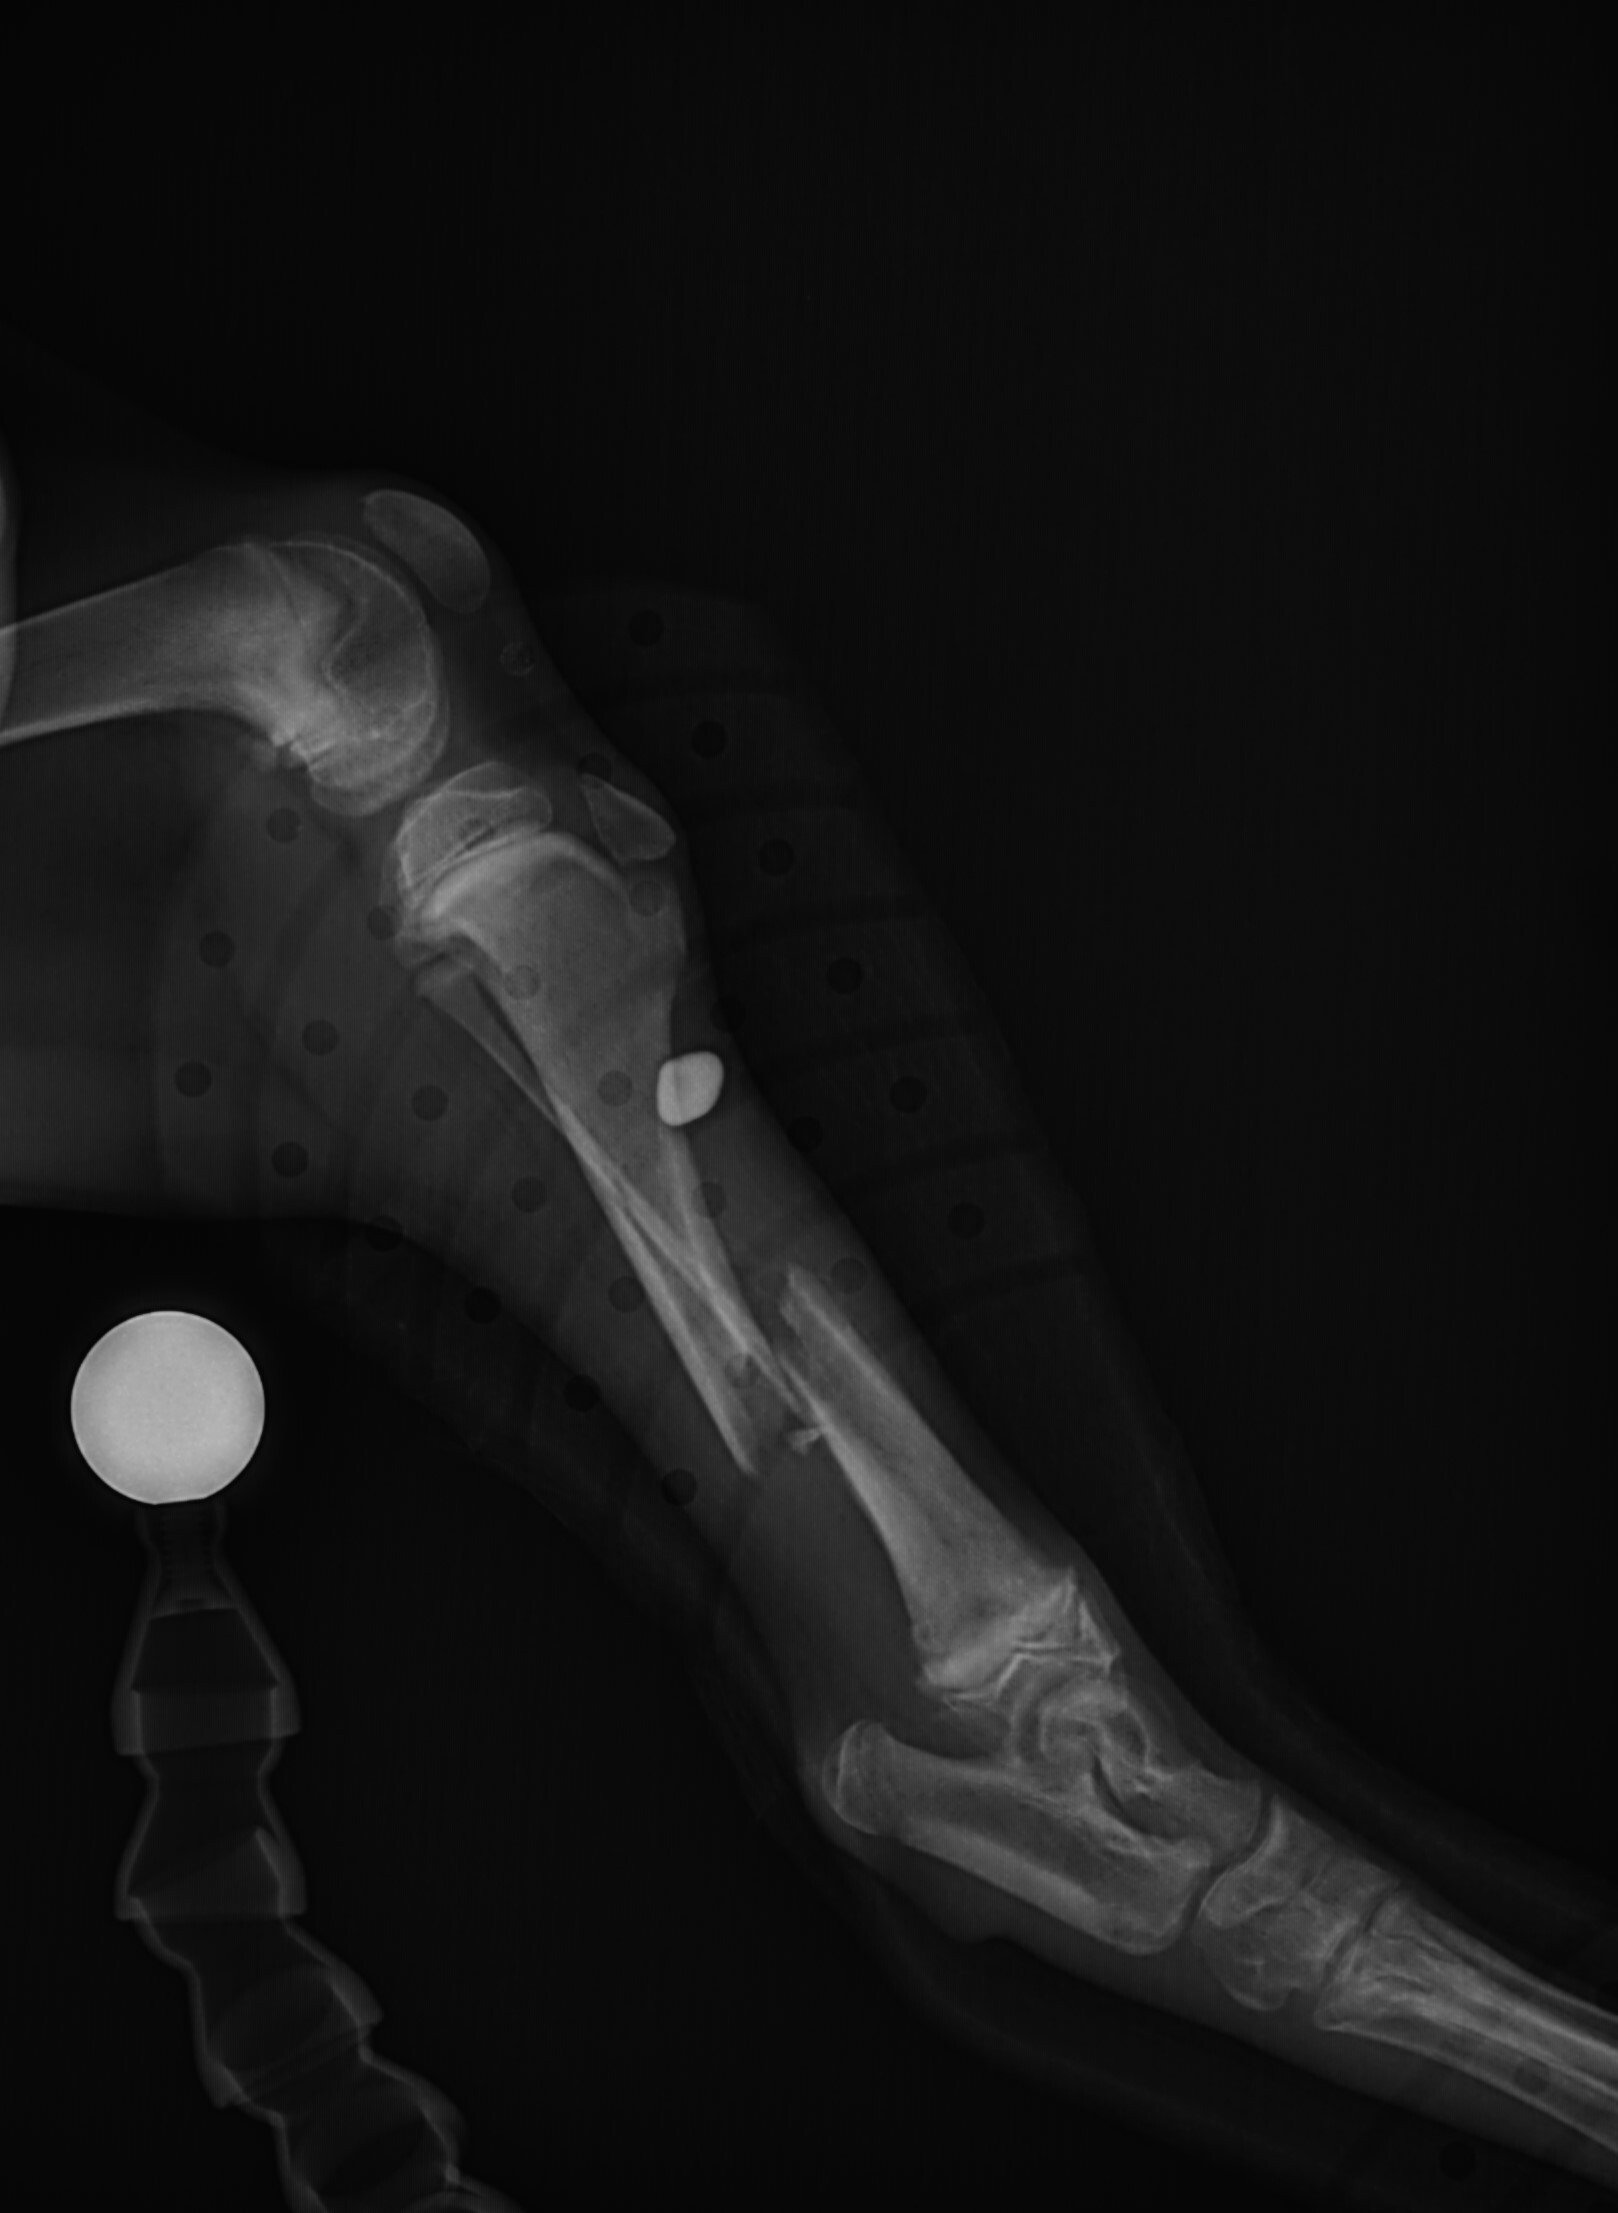

Leg fractures are one of the most common orthopedic problems presented at our clinic and usually result from a traumatic mishap. They can be treated in a variety of ways depending on the location and type of fracture. We can apply a cast to treat certain fractures; however, many fractures will require surgical intervention:

- “Pinning” stabilizes the fracture by inserting a long stainless steel rod into the middle of the bone across the fractured area.

- “Plating” involves attaching a flat stainless steel plate to the bone using screws on either side of the fracture.

Below are x-rays of just a few orthopedic surgeries before and after that Dr. Gose has performed.